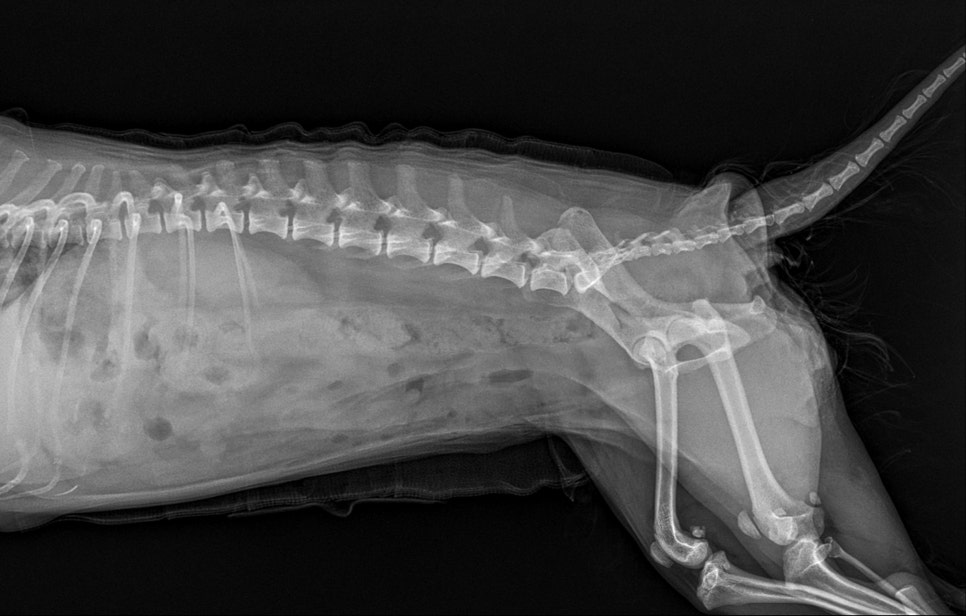

내원 당시 방사선 검사 결과 / 출처: 24시온숲동물의료센터

응급 진료 후 방사선(X-ray)과 초음파 검사 결과, 요도를 막고 있는 큰 결석이 확인되었으며, 이 결석이 요도를 막고 있어 소변 배출이 불가능한 상태였습니다.